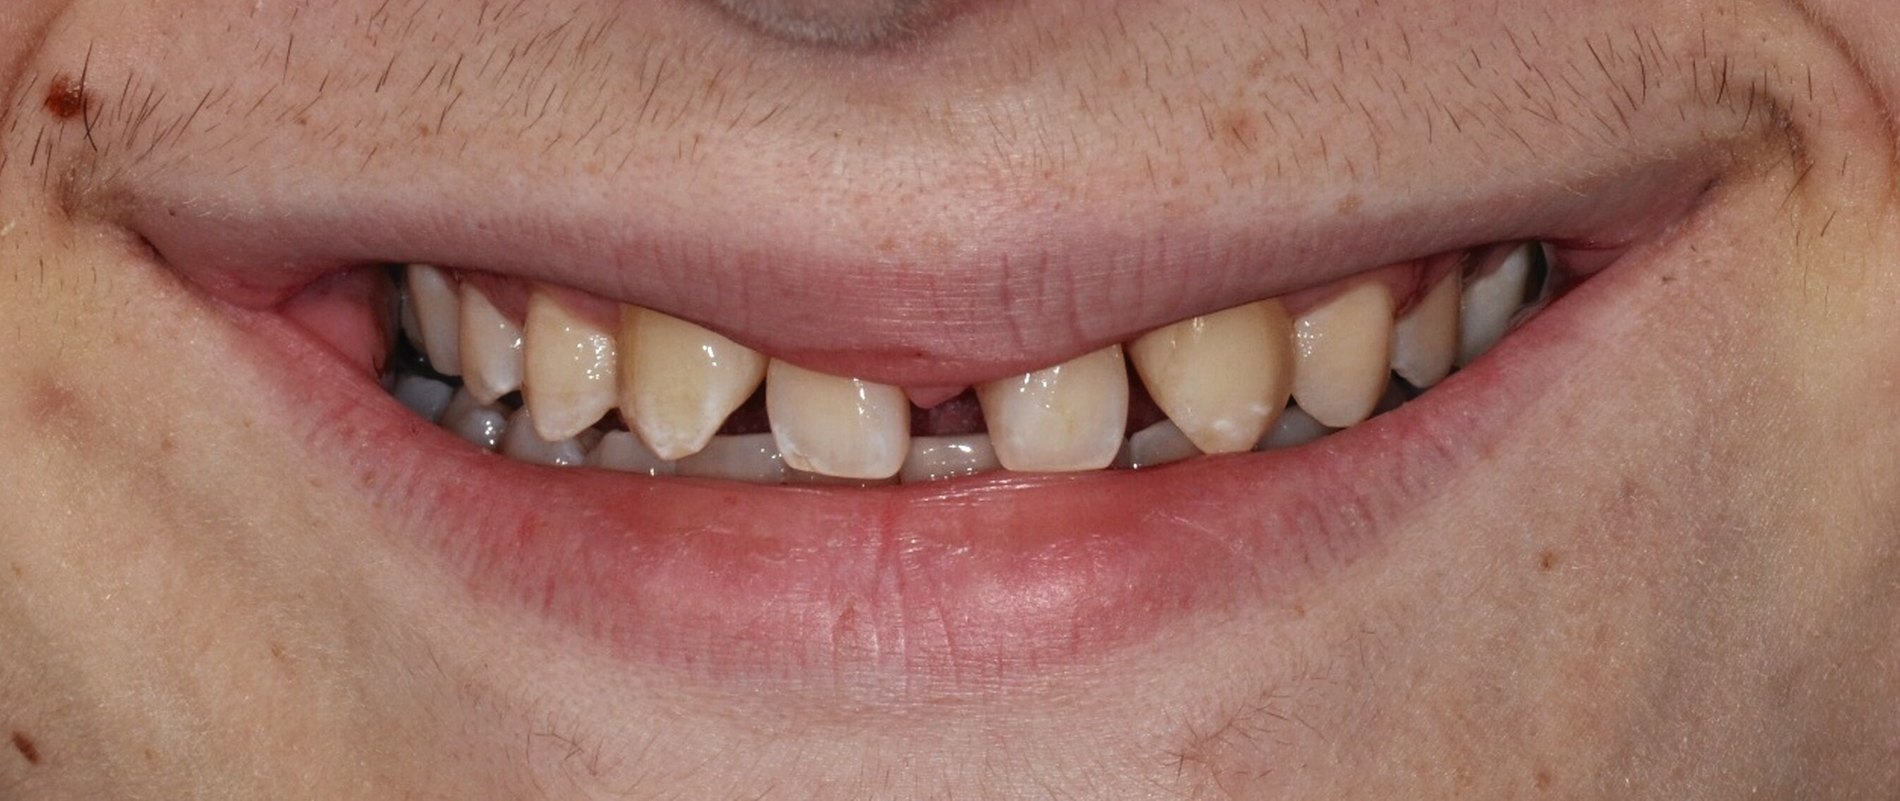

Bei der Erstvorstellung zeigt der Patient ein ausgeprägtes Diastema mediale sowie Restlücken und Asymmetrien im Oberkieferfrontzahnbereich nach kieferorthopädischer Therapie alio loco (Abbildung 1). Aufgrund mangelnder Adhärenz konnten nicht alle kieferorthopädischen Behandlungsziele erreicht werden, was insbesondere aus ästhetischer Sicht Herausforderungen für den restaurativen Lückenschluss mit sich bringt. Erschwerende Faktoren sind die Verschiebung der Mittellinie, die Achsenneigung der Zähne 13, 12, 22 und 23 sowie die inhomogene Lückenverteilung mit ungleich verteilten Lückengrößen (Abbildung 2). Eine erneute kieferorthopädische Korrektur lehnt der Patient allerdings ab. Subjektiv empfindet er insbesondere das kindliche Erscheinungsbild der lückig stehenden, kurz und klein wirkenden seitlichen Schneidezähne als störend. Ziele der Behandlung sind eine präventionsorientierte, ästhetisch-funktionale Rehabilitation des Oberkieferfrontzahnbereichs und eine Harmonisierung des dentofazialen Erscheinungsbildes.